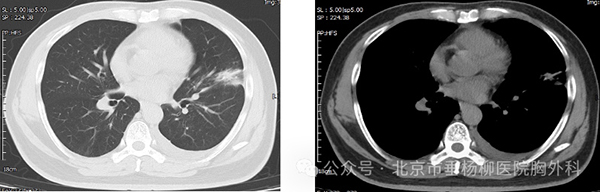

为明确肺部占位是否为恶性肿瘤,还需行CT引导下经皮肺病损穿刺活检术明确病变性质,术中操作顺利,无气胸、咯血等异常;术后穿刺病理:(左肺上叶结节)肺脓肿。最终诊断:肺脓肿,在给予2周规范消炎、化痰等治疗后,再次复查胸部CT,病灶大小较前明显缩小(约2.7*3.3cm),实性成分较前明显减少,最终避免了全麻手术切除,顺利出院。

术后消炎后胸部CT-肺窗 纵隔窗